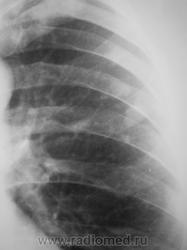

Пациент взят на контроль после проведения профилактической флюорографии.

а в легких изменения?очаговые тени в легких и склеротические изменения тела толкают на мысли о метастатическом поражении.

Сделали "томку".

Мысль всё о метастазах. Клинических проявлений нет никаких? В брюшной полости ничего не растет?

Мы тоже высказали мнение о наличии метастазов. У пациента установлен ( в области) рак предстательной железы, диагноз в ООД вверифицирован.